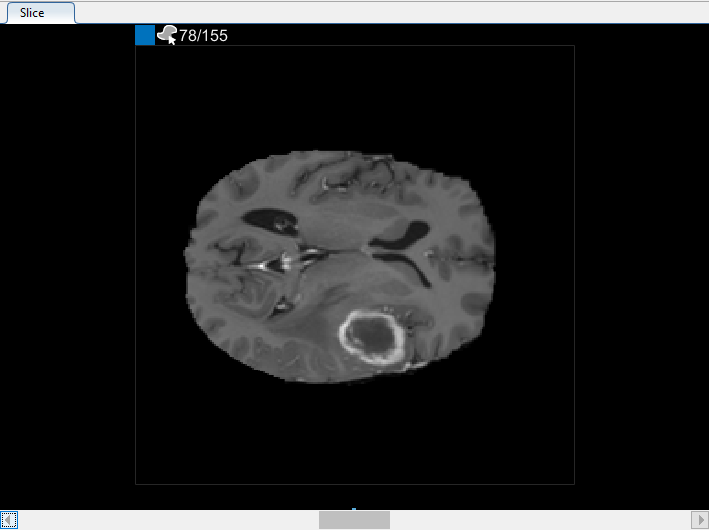

Можно также просмотреть каждый срез объема в панели Среза. Используйте ползунок в нижней части панели, чтобы переместиться от среза до среза. Вы видите опухоль на срезе 35 через срез 88. По умолчанию панель Среза отображает объем, ориентированный вдоль оси X-Y, но можно изменить это использование кнопки в разделе Orientation панели инструментов на вкладке Segmenter. Панель Среза также, где вы используете инструменты для рисования, чтобы задать маску.

В панели Среза перейдите к срезу, где объект сначала появляется, и используйте инструмент для рисования, чтобы пометить объект. В следующем рисунке этот пример использует инструмент Paint Brush, чтобы пометить мозг, но можно использовать любой из инструментов для рисования.

После использования интерполяции проверяйте отдельные срезы, чтобы видеть, создала ли интерполяция удовлетворительные ROI. Обратите внимание на то, что ROI на срезе 71 не заполняет целый объект, который вы хотите сегментировать. Можно вручную настроить ROI с помощью инструмента Paint Brush. В качестве альтернативы можно использовать один из инструментов во вкладке Automate. Например, можно использовать Активные Контуры, чтобы вырастить ROI на срезах, где это не заполняет полный размер опухоли.

В панели Среза перейдите к срезу, где объект сначала появляется, и начните помечать объект на каждом срезе с помощью инструмента для рисования. В следующем рисунке этот пример использует инструмент Paint Brush, чтобы пометить опухоль. Как ранее, можно чертить объект на каждом срезе, где это появляется, или используйте инструменты интерполяции, чтобы привлечь несколько срезов автоматически. После интерполяции можно использовать инструменты для рисования, такие как Средство стирания, чтобы изменить автоматизированную сегментацию на каждом срезе.